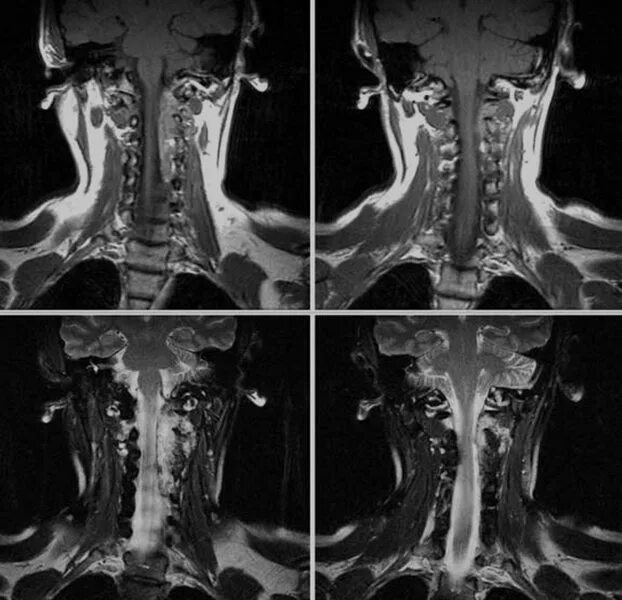

Просмотр снимков мрт